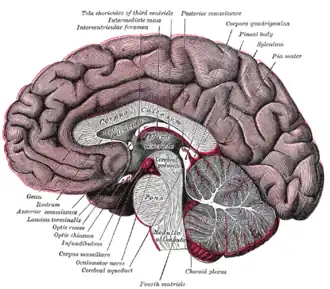

Ромбовидная ямка. Срединный сагиттальный срез головного мозга.

Срединный сагиттальный срез головного мозга. Желудочки головного мозга, вид сбоку.